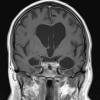

11A1 Pick Dz (Case 11) T2FLAIR - Copy - Copy

11A2 Pick Dz (Case 11) T2FLAIR 2 - Copy - Copy

11A3 Pick Dz (Case 11) T2FLAIR 3 - Copy - Copy

11A4 Pick Dz (Case 11) T1 post Contrast 2 - Copy